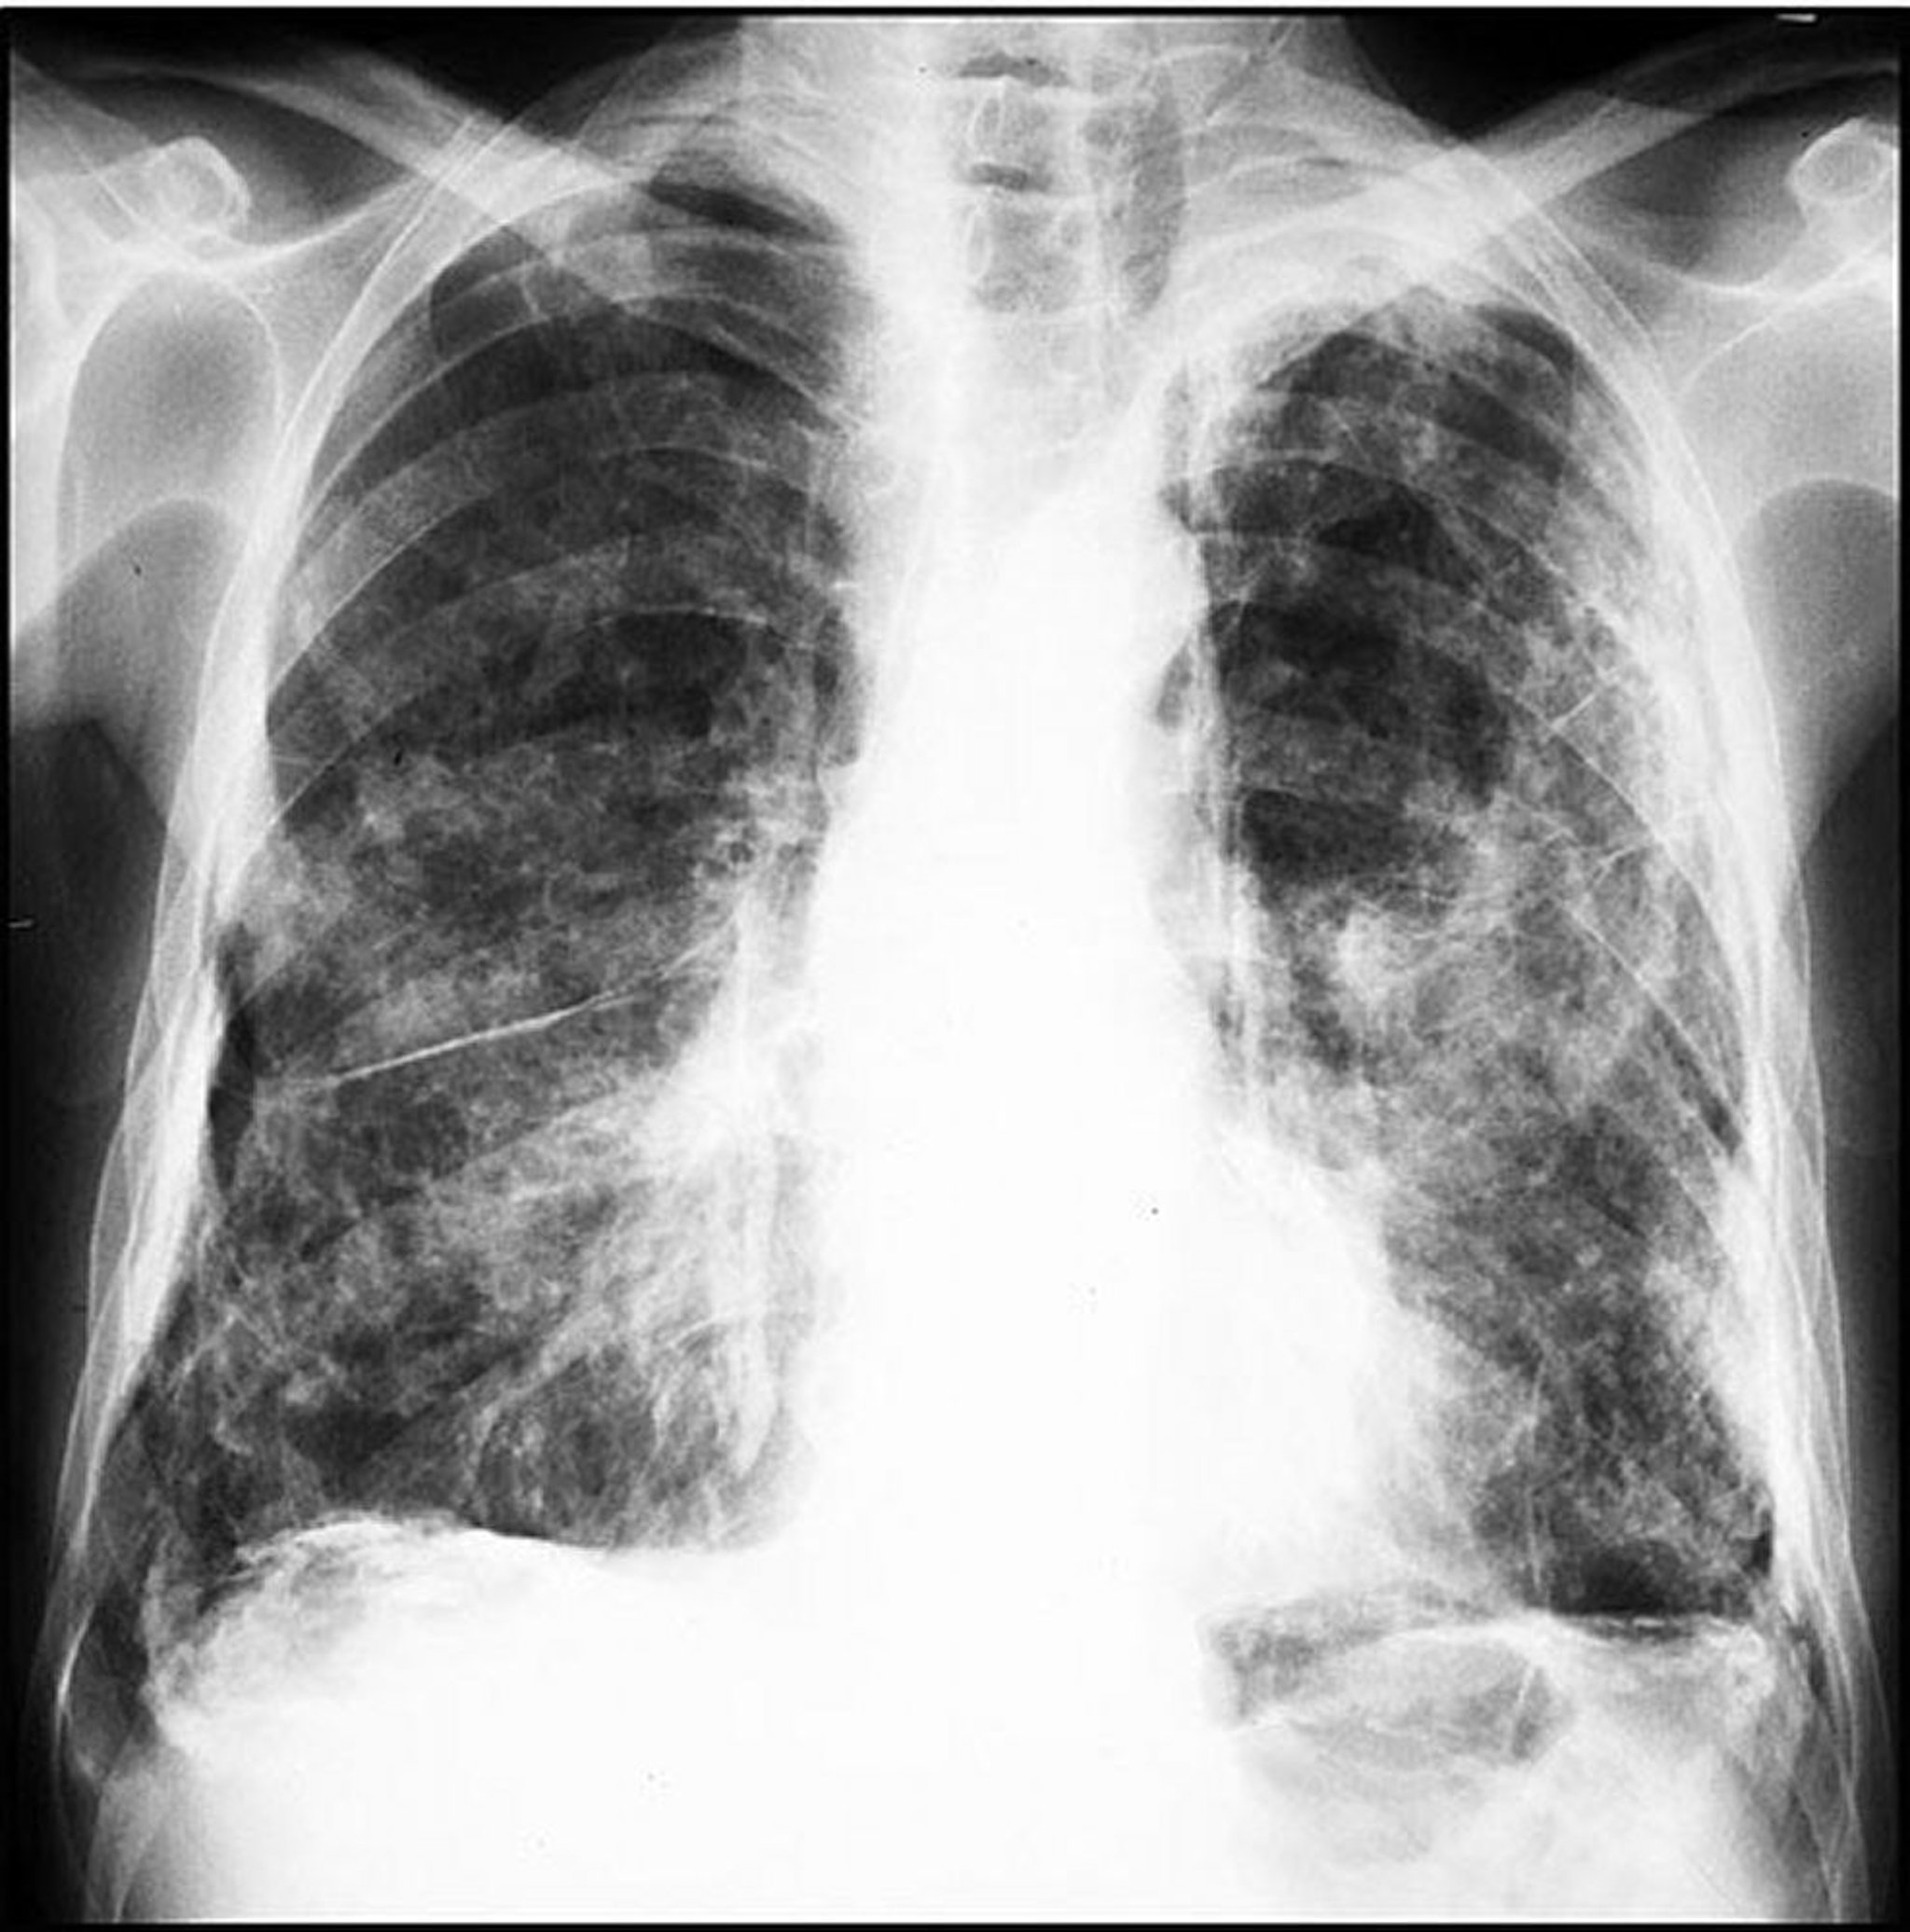

Placche correlate all'amianto (estese)

Image courtesy of David W. Cugell, MD.